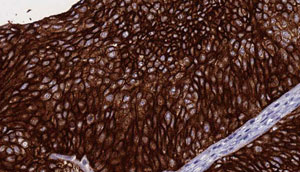

IHC (Immunohistochemistry)

(AAA325817 at 1/100 staining Human urothelial cancer tissue by IHC-P. The sample was formaldehyde fixed and a heat mediated antigen retrieval step in citrate buffer was performed. The sample was then blocked and incubated with the antibody for 1.5 hours at 22 degree C. An HRP conjugated goat anti-rabbit antibody was used as the secondary.)